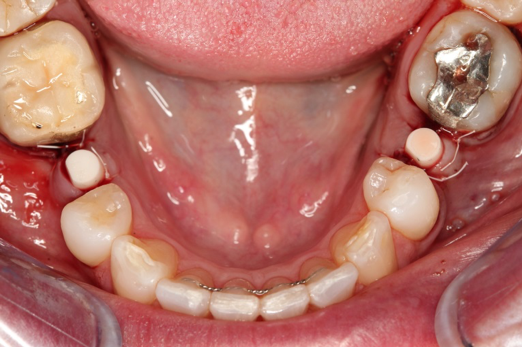

Figure 3 through Figure 5 show the fitting of a one-piece multiple splint using a light-cured acrylic, along with flowable composite to adhere the splint to the three ceramic dental implants. The splint was to remain out of occlusion, without any occlusal forces for the 12-week osseointegration period. The patient was instructed to chew on the other side of her mouth for the 12 weeks before returning to the dental practice for simple removal of the splint. Removal of the splint revealed optimum results. The soft tissues were pink, with keratinized gingival margins completely surrounding the ceramic implants and consistent with what most dentists observe with the periodontium around periodontally healthy natural teeth (Figure 6 and Figure 7).

Fig 6. After splint removal (12 weeks postoperatively).

Fig 7. 12 weeks postoperatively.